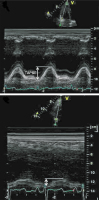

TAPSE

Abbildung 6: Zur Bestimmung der „tricuspid anular plane systolic excursion“ (TAPSE) wird die Distanz der systolischen Exkursion des Trikuspidalanulussegments in longitudinaler Achse von einem Standard-Vierkammerblick aus gemessen.

Trikuspidalklappenanulus

Abbildung 7: Tissue-Doppler des Trikuspidalklappenanulus eines Patienten mit normaler rechtsventrikulärer Funktion.